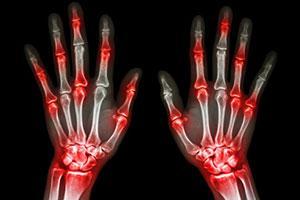

В случае перелома шейки бедра компания МосРентген Центр госпитализирует в Склиф для эндопротезирования.